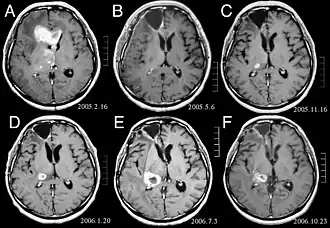

Patiënten lijden aan een verscheidenheid aan karakteristieke symptomen van een focale of multifocale massieve laesie. MRI toont meestal tumoren met homogene contrastversterking in de diepe periventriculaire witte stof. Multifocaliteit en inhomogene versterking zijn typisch voor patiënten met een verzwakt immuunsysteem. Analyse van CZS-lymfoom is uiterst belangrijk bij de differentiële diagnose van hersenneoplasie. Opgemerkt moet worden dat de toediening van corticosteroïden kan leiden tot het volledig verdwijnen van de versterking, waardoor de diagnose van de laesies moeilijk wordt. Als daarom CZS-lymfoom moet worden overwogen bij de differentiële diagnose, moeten corticosteroïden worden vermeden, tenzij het massa-effect een ernstig en onmiddellijk probleem bij de patiënt veroorzaakt.

Hersenmetastasen zijn de meest voorkomende intracraniële neoplasmata bij volwassenen en komen tien keer vaker voor dan primaire hersentumoren. Ze stappen op 20 tot 40 procent van de volwassenen met kanker en worden voornamelijk geassocieerd met long- en borstkanker en melanoom. Deze laesies zijn het gevolg van de verspreiding van kankercellen door de bloedbaan en komen meestal voor op de kruising van grijze en witte stof, waar de dwarsdoorsnede van bloedvaten verandert, waardoor tumorcelembolie wordt opgesloten . 80 procent van de laesies komt voor in de hersenhelften, procent in het cerebellum en 5 procent in de hersenstam. Ongeveer 80 procent van de patiënten heeft een voorgeschiedenis van systemische kanker en 70 procent heeft meerdere hersenmetastasen.

Hersenmetastasen zijn de meest voorkomende intracraniële neoplasmata bij volwassenen en komen tien keer vaker voor dan primaire hersentumoren. Ze stappen op 20 tot 40 procent van de volwassenen met kanker en worden voornamelijk geassocieerd met long-en borstkanker en melanoom. Deze laesies zijn het gevolg van de verspreiding van kankercellen door de bloedbaan en komen meestal voor op de kruising van grijze en witte stof, waar de dwarsdoorsnede van bloedvaten verandert, waardoor tumorcelembolie wordt opgesloten. 80 procent van de laesies komt voor in de hersenhelften, procent in het cerebellum en 5 procent in de hersenstam. Ongeveer 80 procent van de patiënten heeft een voorgeschiedenis van systemische kanker en 70 procent heeft meerdere hersenmetastasen.

De literatuur laat gelijkwaardige resultaten zien voor chirurgie en radiochirurgie. Dit laatste lijkt handiger, effectiever en veiliger voor kleine laesies of in gebieden die niet toegankelijk zijn voor chirurgie. Radiochirurgie is een verstandig alternatief voor patiënten die om medische redenen niet geopereerd kunnen worden. Chirurgie is echter duidelijk de optimale methode om weefsels te verkrijgen voor diagnose en om de laesies te verwijderen die een massa-effect veroorzaken. Daarom moeten radiochirurgie en chirurgie beter worden beschouwd als twee complementaire maar verschillende methoden die moeten worden toegepast, afhankelijk van de verschillende situatie van de patiënt. Voor bijna 50 procent van de patiënten met een of twee hersenmetastasen komt niet in aanmerking voor chirurgische verwijdering vanwege de ontoegankelijkheid van de laesies, de omvang van de systemische ziekte of andere factoren. Deze en andere patiënten met meerdere metastasen krijgen gewoonlijk panencefale bestralingstherapie als standaardbehandeling. Bereik eigenlijk tot bijna 50 procent van hen met deze therapie een verbetering van neurologische symptomen en 50 tot 70 procent een merkbare reactie. Chemotherapie wordt zelden primair gebruikt voor hersenmetastasen.

Voor de meeste patiënten met hersenmetastasen is de mediane overleving slechts vier tot zes maanden na panencefale bestralingstherapie. Patiënten jonger dan 60 jaar met discrete laesies en gecontroleerde systemische ziekte kunnen echter een langere overleving bereiken omdat ze een agressievere behandelingsbenadering kunnen verdragen.